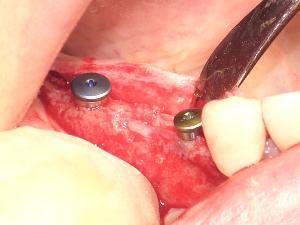

人工歯根(フィクスチャー)を顎の骨に埋め込みます。

当院では安全性と確実性を重視し、主に2回法を採用しています。

事前のCTシミュレーションをもとに作製したサージカルガイドを使用し、位置・角度・深さを精密にコントロールしながら埋入します。